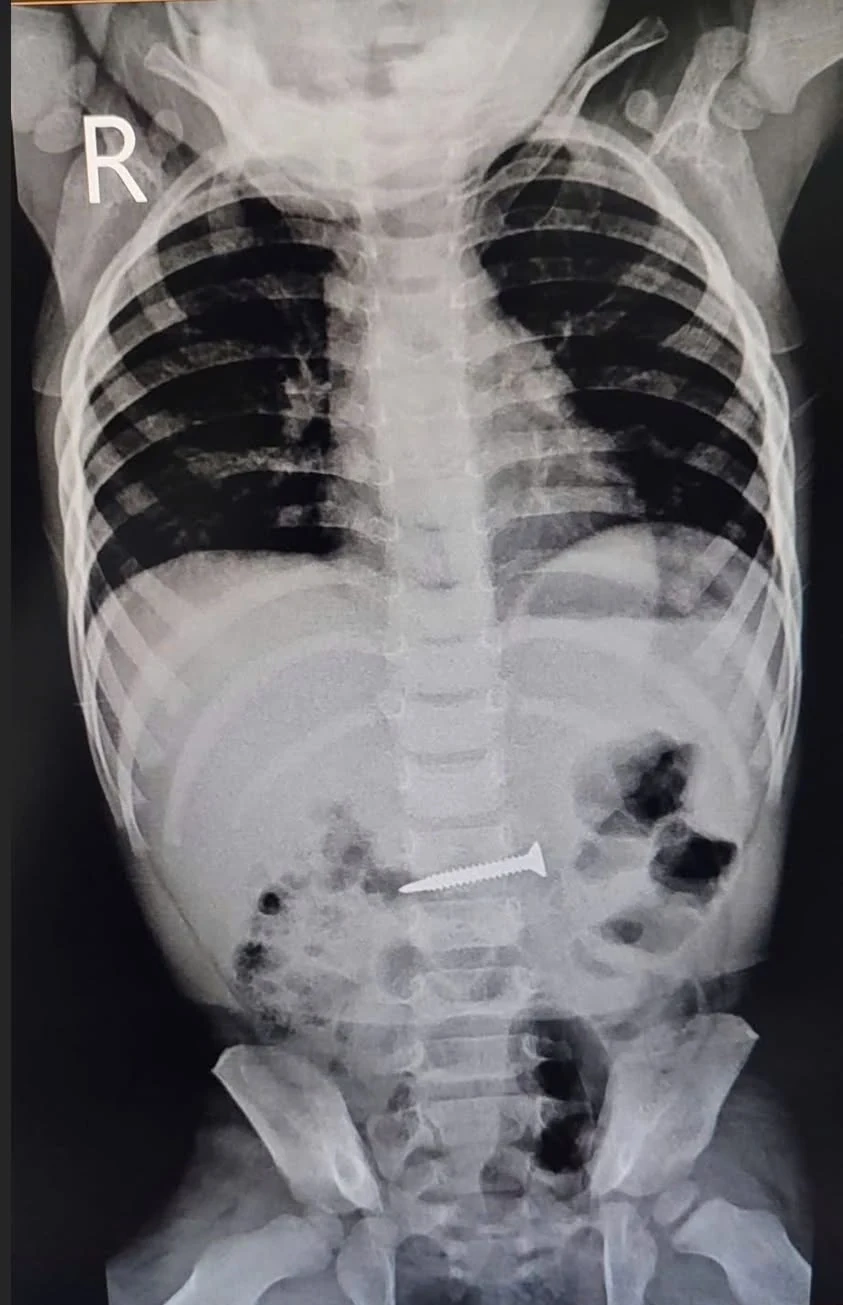

Kết quả chụp X-quang của bệnh nhi.

Kết quả chụp X-quang cho thấy hình ảnh dị vật cản quang kim khí sắc nhọn trong ổ bụng, nằm ở vị trí ngang mức đốt sống L2-L3. Trước tình trạng nguy hiểm, ê-kíp bác sĩ đã tổ chức hội chẩn và quyết định thực hiện thủ thuật nội soi dạ dày có gây mê để lấy dị vật ra ngoài.